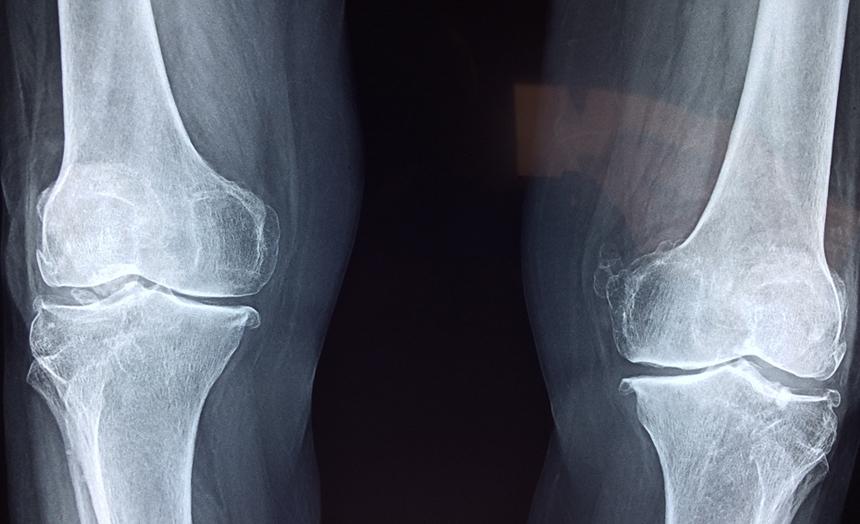

- Knee joint replacement (TKR)

- Complete imaging support including 1.5 Tesla MRI (magnetic resonance imaging)